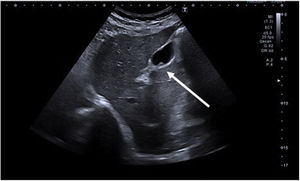

| Adenomiomatosis | Proliferación de epitelio con hipertrofia de la capa muscular con invaginaciones de mucosa hipertrófica a través de la capa muscular engrosada (sinusoides de Rokitansky-Aschoff). Puede ser difusa, segmentaria o focal | Engrosamiento de la pared con espacios quÃsticos y el artefacto «en cola de cometa» (foco hiperecoico con reverberación acústica posterior en forma de triángulo invertido, con disminución gradual de la ecogenicidad (fig. 2) |